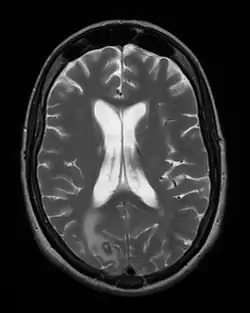

W celu dokładnego diagnozowania zmian w organizmie można zobrazować całą serię jego przekrojów poprzecznych przy pomocy promieni rentgenowskich - metoda ta nosi nazwę tomografii komputerowej (TK, CT)[1].

Spektroskopia magnetycznego rezonansu jądrowego (RM, MR, NMR, MRI) również wykorzystuje serię przekrojów poprzecznych, które pozwalają na wizualizację danych w formie obrazów, umożliwiających ich ocenę przez człowieka[1].